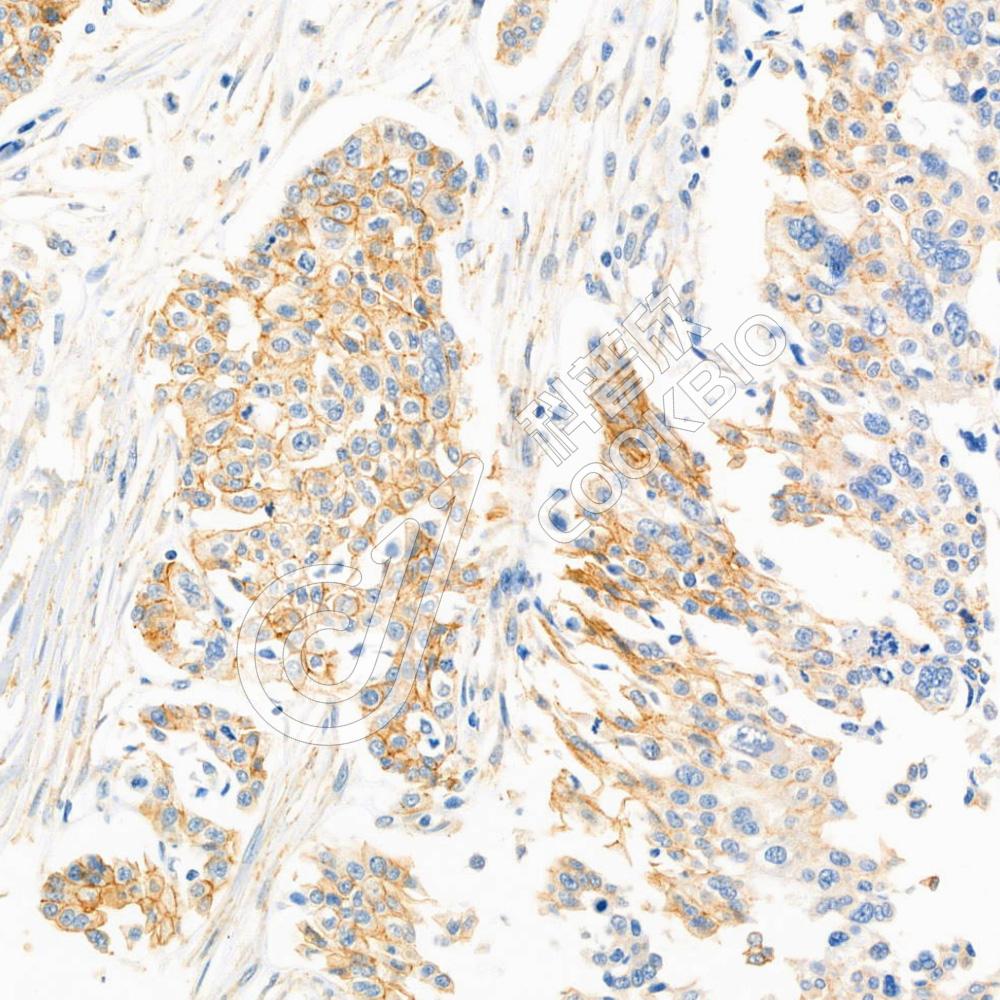

IHC检测Occludin蛋白(货号 K1334203).

样品: 人卵巢癌, 4%多聚甲醛 (货号KSG1101) 固定12-24小时.

抗原修复: 柠檬酸抗原修复液(干粉, pH 6.0) (KSG1201), 98℃, 20分钟.

—抗: 1: 1000稀释, 4℃ 孵育过夜.

二抗: S-vision免疫组化多聚二抗(山羊抗兔),即用型 (货号KB3906), 室温孵育20分钟.